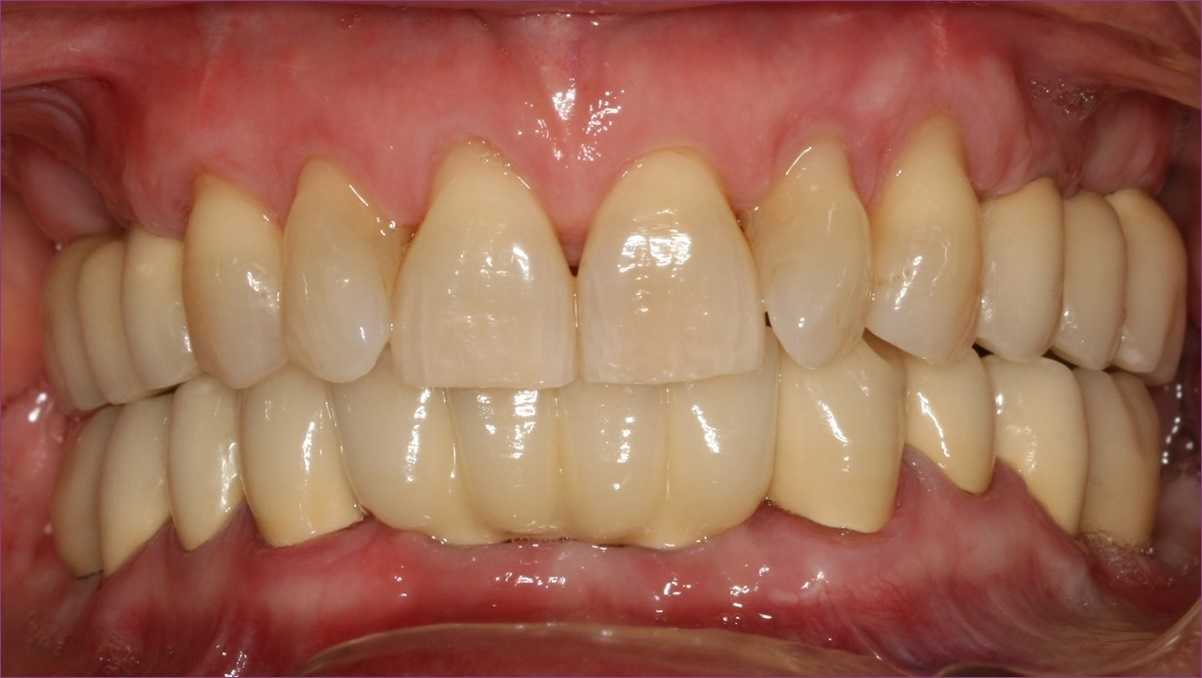

Miután sikerült a fogágypusztulást megállítani, és ezt az állapotot stabilizálni, megtörtént a foghiányok végleges pótlása implantátumok és fémkerámia fogpótlások segítségével. Ezalatt a pácienssel és a dentálhigiénikus kolléganővel közösen kialakítottunk egy olyan fogmosási rutint, amellyel a hölgy fenn tudja tartani a gyulladásmentes állapotot.

Páciensünk figyelmét felhívtuk arra, hogy fogágybetegségéből adódóan három havonta-félévente javasolt kontrollvizsgálatra járnia, hogy az új fogpótlásai időtállóak legyenek, és a betegség ne újuljon ki.

Páciensünk végtelenül elégedett volt a végeredménnyel, és azóta is rendszeresen látjuk az ellenőrzések során.